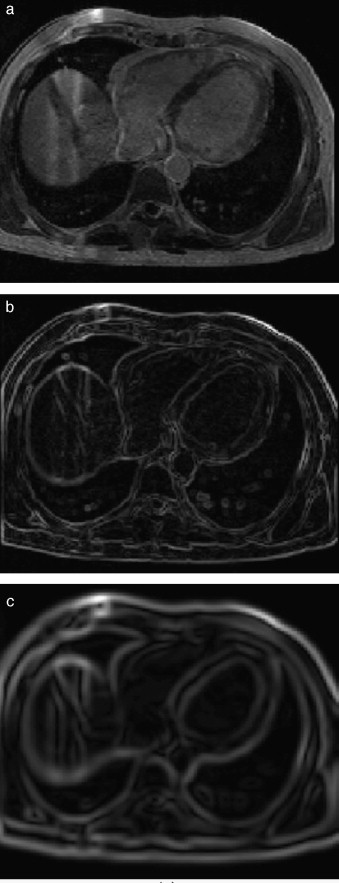

En la figura 7 se presenta la aplicación de dos rutinas del cálculo del gradiente en IRM cardiovascular. Obsérvese como los contornos son mejorados y se puede distinguir mejor el músculo miocardio y el ventrículo izquierdo. En la figura 7 .b se aplicó el operador Sobel en las direcciones x,y,z. En la figura 7 .c se presenta el resultado de aplicar el filtro itk::GradientMagnitudeRecursiveGaussianImageFilter[20]. Este filtro calcula la magnitud de la imagen gradiente por cada pixel o voxel. El proceso computacional consiste en primero suavizar la imagen a través de la convolución con una máscara Gaussiana y luego aplicar el operador diferencial.

Aplicación de las rutinas de módulo de una imagen gradiente. (a) IRM ...

Figura 7.

Aplicación de las rutinas de módulo de una imagen gradiente. (a) IRM cardiovascular original, solo se visualiza el corte axial número 33. (b) Aplicación del operador Sobel en x,y,z en la imagen (a). (c) Imagen módulo del gradiente de (a) empleando itk::GradientMagnitudeRecursiveGaussianImageFilter .

En la figura 8 se presenta la aplicación de la rutina del filtro sigmoid a partir de la imagen módulo gradiente mostrada en la figura 7 .c.

Reforzado de bordes empleando el filtro sigmoid. (a) Imagen módulo gradiente de ...

Figura 8.

Reforzado de bordes empleando el filtro sigmoid . (a) Imagen módulo gradiente de IRM cardiovascular l. (b) Imagen (a) con los bordes reforzados empleando en itk::SigmoidImageFilter .